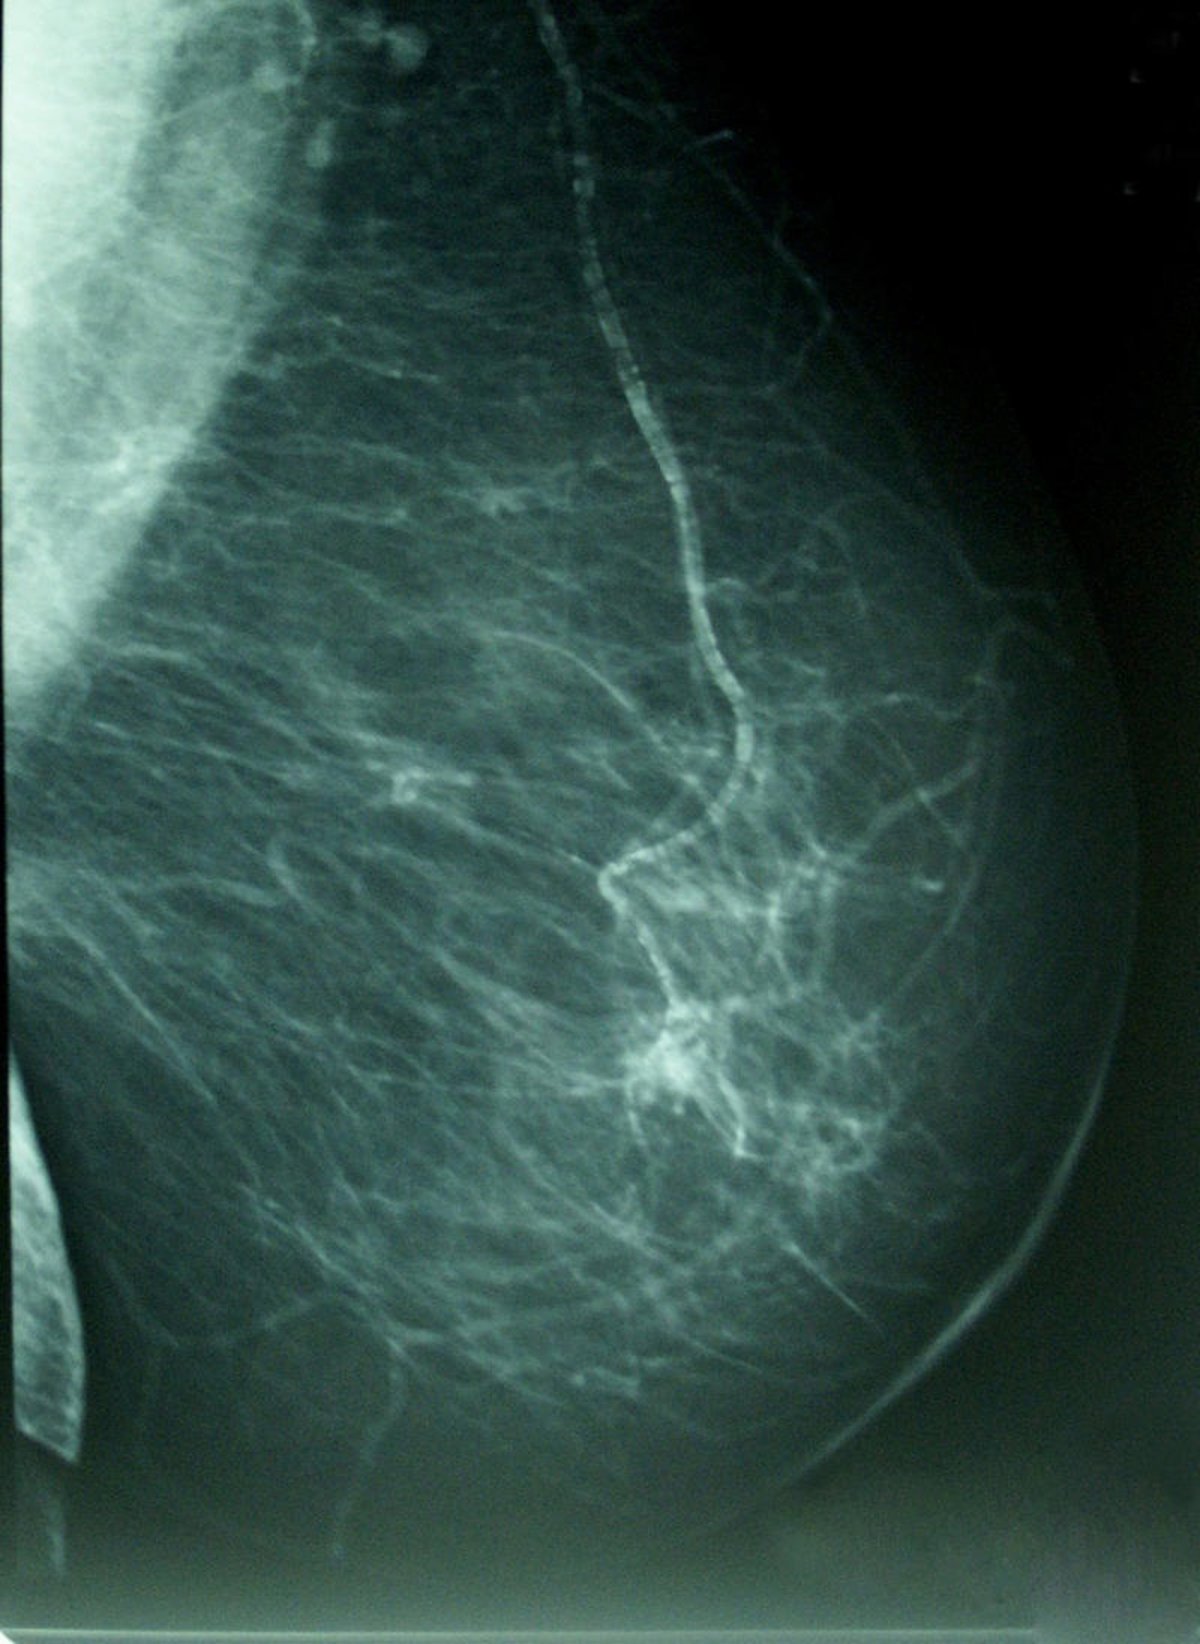

El estudio, publicado en la revista 'Breast Cancer Research and Treatment', explora la influencia de determinadas características con dicha densidad - la proporción de tejido radiológicamente blanco en la mamografía-, que es reconocido como un marcador de riesgo de cáncer de mama.

La investigación, realizada sobre una muestra 3.574 mujeres con edades comprendidas entre los 45 y los 68 años, analiza la influencia de ciertas características del nacimiento y la infancia de las mujeres con su densidad mamógrafica, un importante marcador de riesgo para cáncer de mama.

Estos resultados se apoyan además en diversos estudios publicados unos años antes, en la reunión anual de 2010 de la Asociación Americana para la Investigación del Cáncer (AACR, por sus siglas en inglés) se presentaron varios estudios que mostraban cómo las mujeres con una densidad igual o mayor al 75 por ciento en una mamografía tienen de cuatro a cinco veces más riesgo de cáncer de mama que las mujeres con baja densidad.